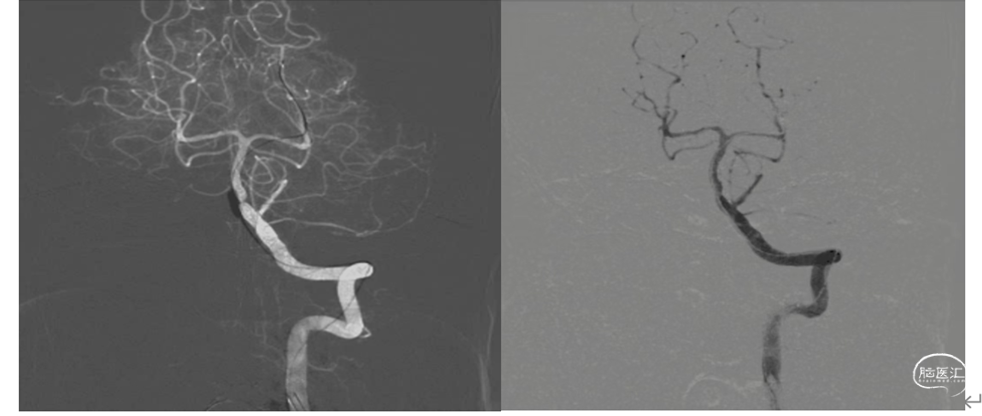

康复期间进行性加重,已超过了静脉溶栓治疗黄金时间,拟行血管内治疗机械再通。脑血管造影显示:基底动脉起始部闭塞,下图

血管内支架机械取栓:

更换8F动脉鞘,0.035in泥鳅导丝携带5F单弯造影导管和8F导引导管同轴到达左

侧椎动脉V1段起到通路和支撑作用。

释放取栓支架:

将6X30mm支架释放于基底动脉尖部与左侧大脑后动脉起始部。支架放置5分钟使支架充分展开,微造影可见基底动脉血流通畅。微造影可见基底动脉尖和双侧大脑后显影。

抽-拉结合取栓

1.裸支架导丝:缓慢拔出微导管于体外,最大限度增加中间导管管腔,有利于抽吸。

2、充分抽吸:跟进中间导管至基底动脉超始部,利用50mL自制负压卡口注射器连接中间导管进行负压抽吸。抽吸出黯红色血栓。

3.回拉支架:负压抽吸中间导管的同时,将取栓支架缓慢拉入中间导管撤出体外。

4.抽吸清理通路:接续二次抽吸中间导管直至血流通畅。

检查取栓结果:

抽吸除少了血栓,造影显示:基底动脉血流通畅。远端供血良好,双侧大脑后动脉供血良好。基底动脉中下段重度狭窄。